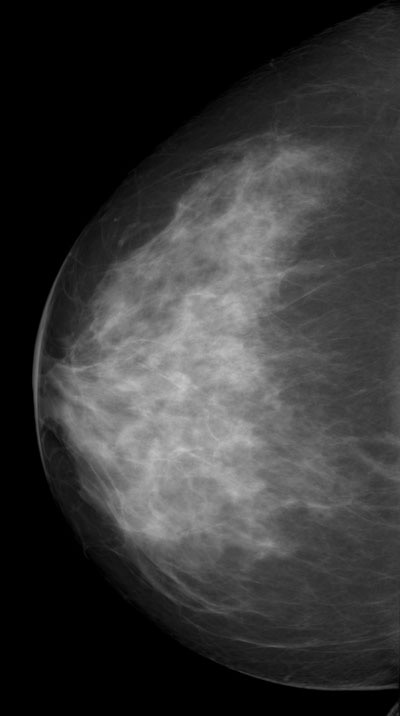

◂Breast Anatomy